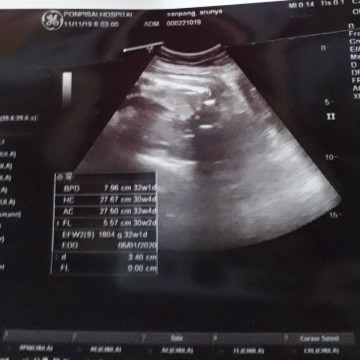

คุณแม่ๆค่ะขอถามหน่อยค่ะ เด็กนอนท่าก้นปกติดีไหมค่ะ แล้วเด็กจะกลับตัวไหมค่ะ 30Wค่ะ

ท่าก้น เป็นท่านอนเอาก้นลง ไม่กลับหัวค่ะ แต่ยังมีเวลาอีกหลายสัปดาห์ที่จะกลับหัวค่ะ ถ้าแม่จะคลอดเองนะคะ ใกล้ๆ กำหนดคลอดมาลุ้นอีกทีค่ะว่าจะกลับหัวมั้ย